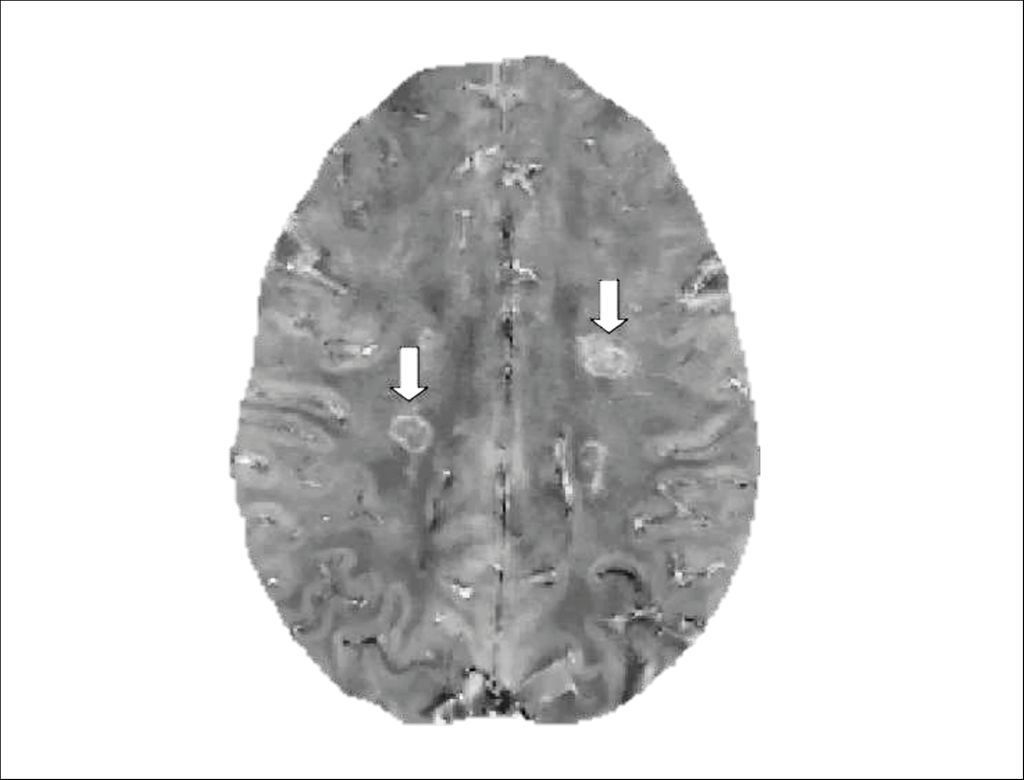

Fig. 1: Example of paramagnetic rim lesions (PRLs) on quantitative susceptibility mapping (QSM). PRLs are indicated by arrows and are characterized by a hyperintense rim reflecting iron accumulation (image modified from Cagol et al. 2023)8

On MRI, PRLs are identified using susceptibility-based sequences, such as susceptibility-weighted imaging (SWI), phase imaging, or quantitative susceptibility mapping (QSM). High-field MRI improves sensitivity, but PRLs can also be detected at 3T and 1.5T with optimized protocols.3

Chronic active lesions can be investigated in vivo using complementary imaging approaches. Each modality captures a different aspect of the underlying biology, reflecting either persistent inflammatory activity or its slow structural consequences.3 Susceptibility-based magnetic resonance imaging (MRI) sequences enable the visualization of iron accumulation at the lesion edge, where chronic inflammatory activity is concentrated. Using this approach, chronic active lesions appear as paramagnetic rim lesions (PRLs), characterized by a rim of paramagnetic signal surrounding a T2-hyperintense lesion core. In parallel, conventional MRI can capture the dynamic footprint of chronic lesion activity over time: on longitudinal T1- or T2-weighted imaging, these lesions may show gradual, concentric enlargement and are therefore termed slowly expanding lesions (SELs). Beyond MRI, chronic lesion inflammation can also be assessed using 18kDa translocator protein positron emission tomography (TSPO-PET), which targets the translocator protein expressed by activated microglia and macrophages. While TSPO-PET provides a more direct measure of innate immune activation, its clinical applicability is limited by low spatial resolution, limited availability, and radiation exposure.